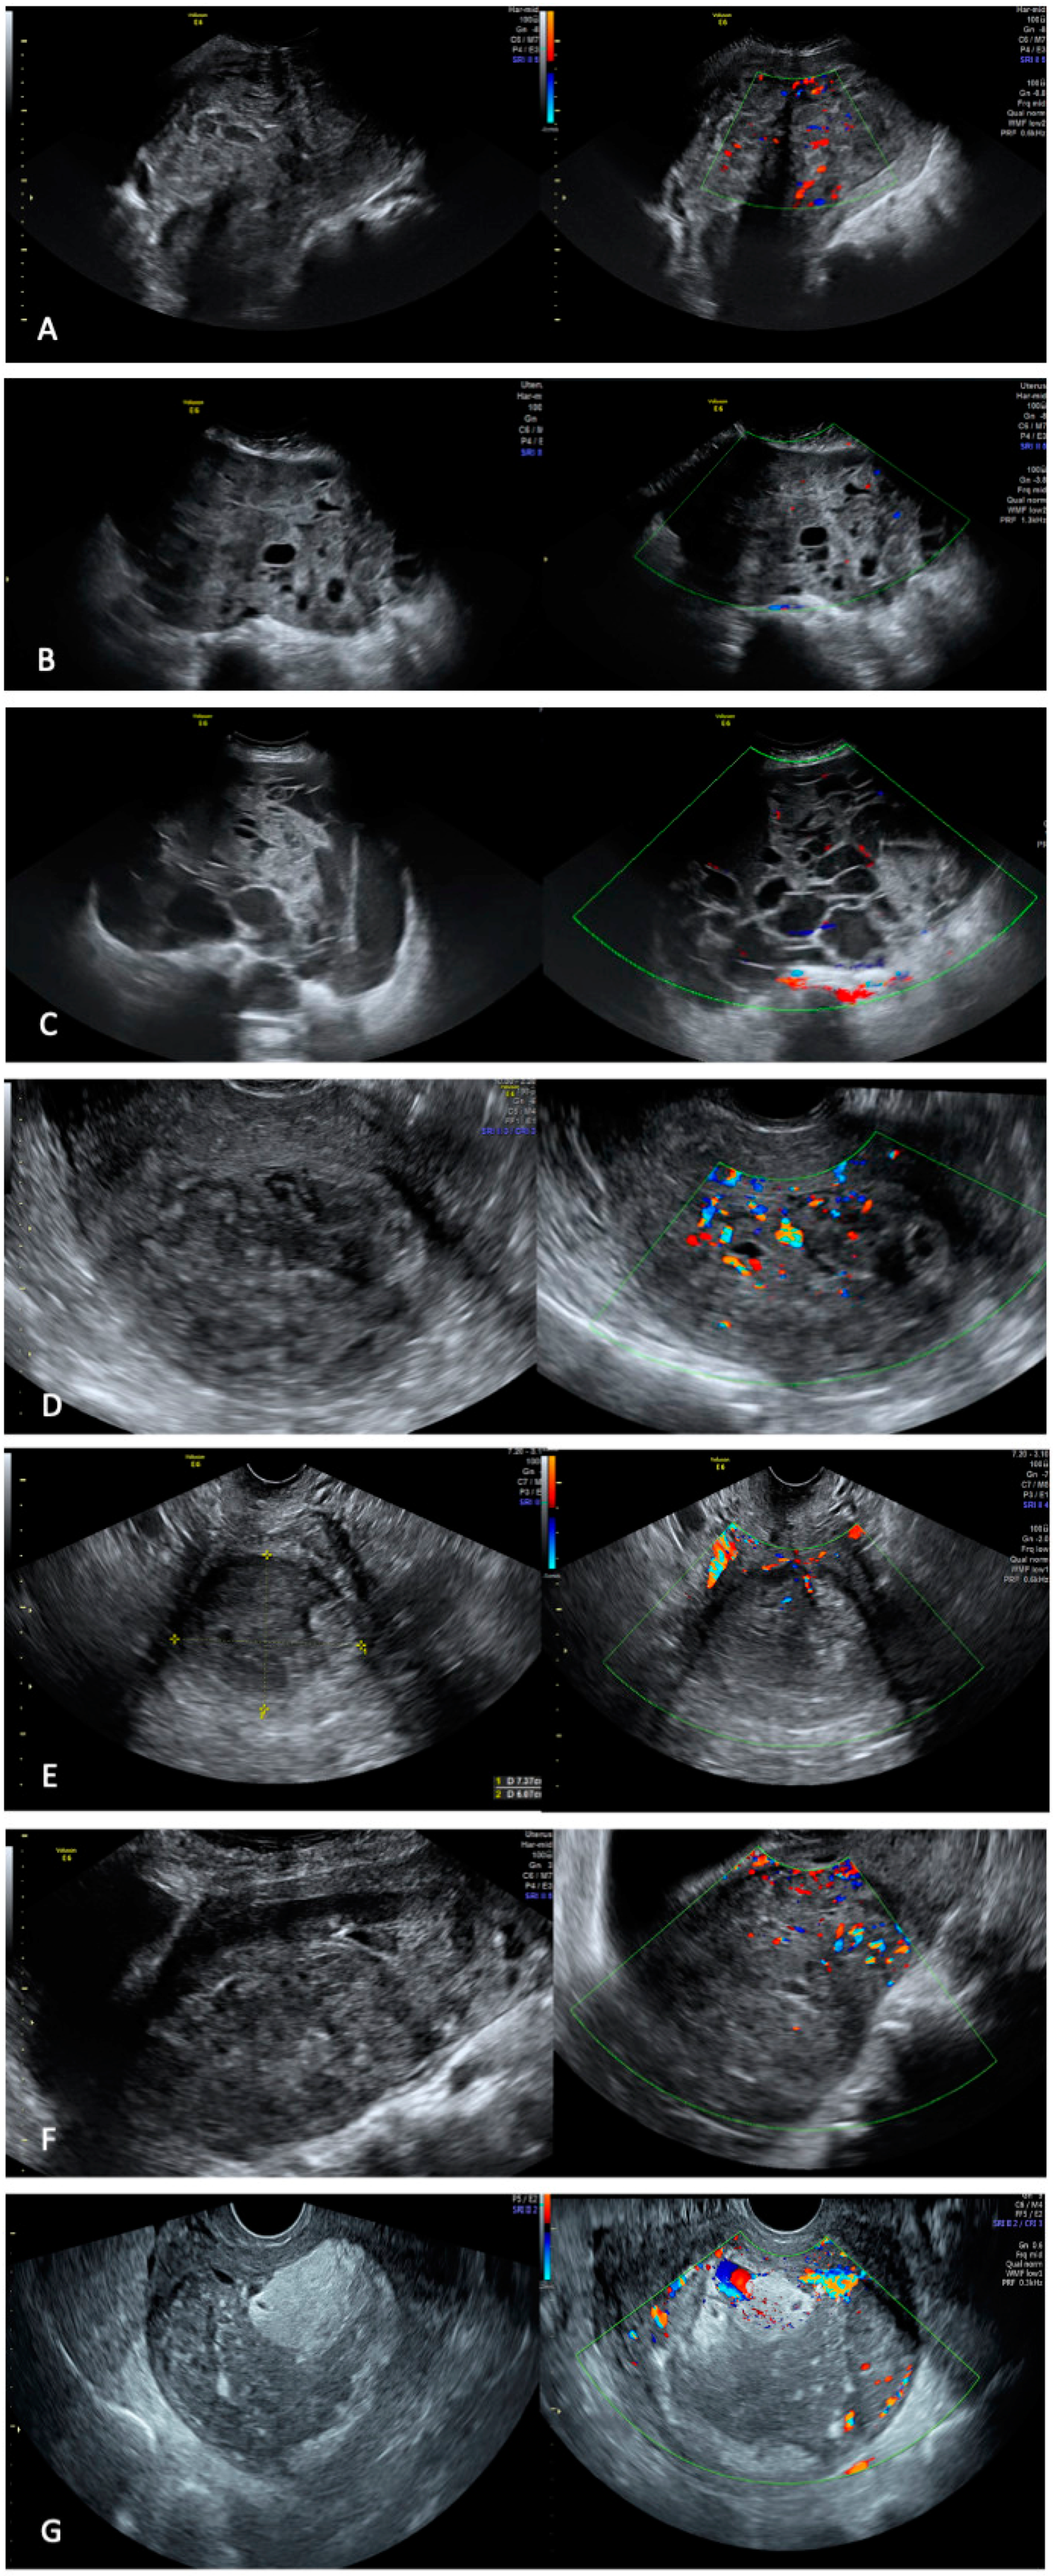

- Russo, C.; Camilli, S.; Martire, F.G.; Di Giovanni, A.; Lazzeri, L.; Malzoni, M.; Zupi, E.; Exacoustos, C. Ultrasound Features of Highly Vascularized Uterine Myomas (Uterine Smooth Muscle Tumors) and Correlation with Histopathology. Ultrasound Obstet. Gynecol. Off. J. Int. Soc. Ultrasound Obstet. Gynecol. 2022, 60, 269–276. [Google Scholar] [CrossRef]

| Characteristics | Quantification/Measurement |

|---|---|

| Age (mean ± sd) | 50.2 ± 7.0 |

| Ca125 (mean ± sd) | 28.8 ± 15 |

| Number of lesions, n (%) | |

| Single | 5 (71.4%) |

| Multiple | 2 (28.6%) |

| Largest diameter (mean ± sd), mm | 152.2 ± 91 |

| The echogenicity of solid tissue, n (%) | |

| Homogeneous | 0 |

| Inhomogeneous | 7 (100%) |

| Tumor borders, n (%) | |

| Regular | 1 (14.3%) |

| Irregular | 6 (85.7%) |

| Shadowing, n (%) No Yes | 3 (42.9%) 4 (57.1%) |

| Vascularization, n (%) Peripheral Intralesional | 0 7 (100%) |

| Color score, n (%) 1−2 3−4 | 4 (57.1%) 3 (42.9%) |

| Cystic areas, n (%) No Yes | 1 (14.3%) 6 (85.7%) |

| Consistency, n (%) Hard Soft | 0 7 (100%) |